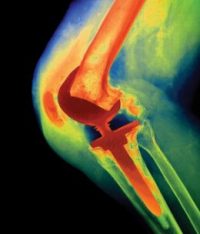

Periprosthetic joint infection (PJI) is one of the most challenging and frequent complications after lower-extremity joint (hip and knee) arthroplasty. The inaugural Periprosthetic Conference has an internationally renowned faculty who will discuss all aspects…